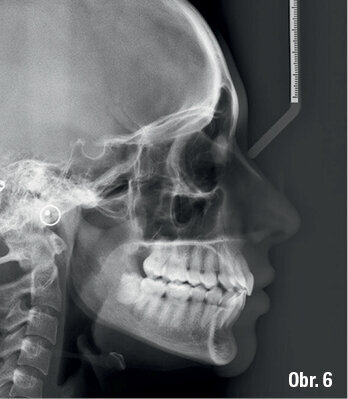

Klinický výsledek byl vynikající, postavení molárů i špičáků v I. třídě, vyhovující překus a předkus. I profil dolní třetiny obličeje byl výrazně lepší.

Na překrytí kefalometrických snímků je zřejmá distalizace molárů o 6 mm bez výraznějšího sklonu a s ideálním bukolingválním sklonem řezáků. Tahy druhé třídy umožnily protrakci mandibuly o 1,5 mm. Jako retenční aparáty jsme zvolili Vivera retainery (Align Technology) (obr. 6, 7a–c, 8a–c).